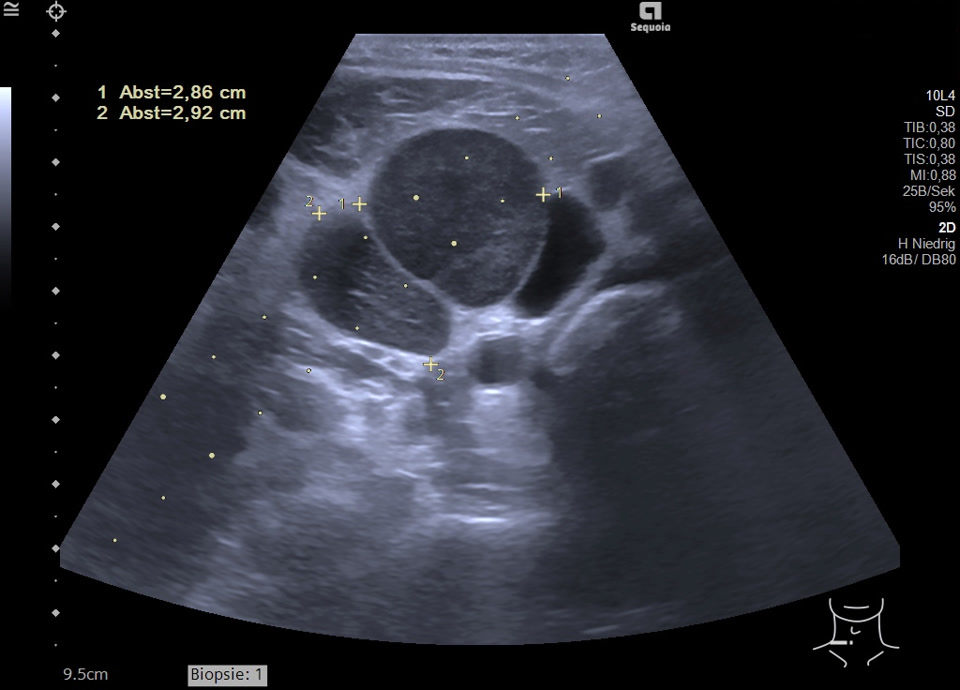

Malignitätsuspekte Raumforderung retroperitoneal und die A. mesenterica superior ummauernd (siehe Markierung), sonographische Punktion ergibt ein Non-Hodgkin Lymphom der B-Zell-Reihe (anaplastische Morphologie)

Malignitätsuspekte Raumforderung retroperitoneal und die A. mesenterica superior ummauernd, sonographische Punktion ergibt ein Non-Hodgkin Lymphom der B-Zell-Reihe (anaplastische Morphologie)